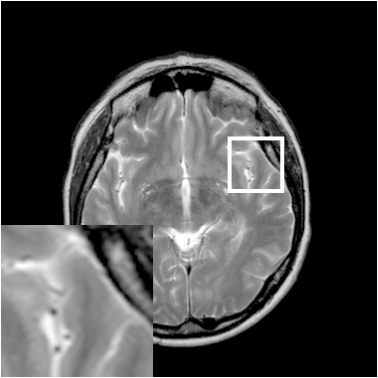

Figure 8: Reconstruction results for 25% cartesian sampling. (a) Original. (b)-(h) Reconstructed images. (i)-(n) The errors of six CSMRI methods.

As shown in Figs. 7, 8 and 9, Sparse MRI and DLMRI have a lot of unpleasant artifacts, Residual learning and U-net can eliminate most of artifacts, but are not ideal for restoring image details. However, the proposed method can reconstruct better MR images, which outperforms other competitive methods in visualization of structures reconstruction and artifacts removal. Meanwhile, we can see from the absolute error residuals for three sampling experiments that the proposed MDN algorithm restores a finer detail structure than other algorithms. Moreover, we present the PSNR and SSIM values in Table I for different algorithms, sampling masks and sampling rates. It is demonstrated that the proposed method provides better reconstruction performance and visual results than other competitive methods. We can also see the obvious improvement of all algorithms over zero-filling both in visualization. In particular, a higher SSIM value of Sparse MRI appears when using 30% variable density random sampling, however, Sparse MRI generates more artifacts than the proposed MDN.